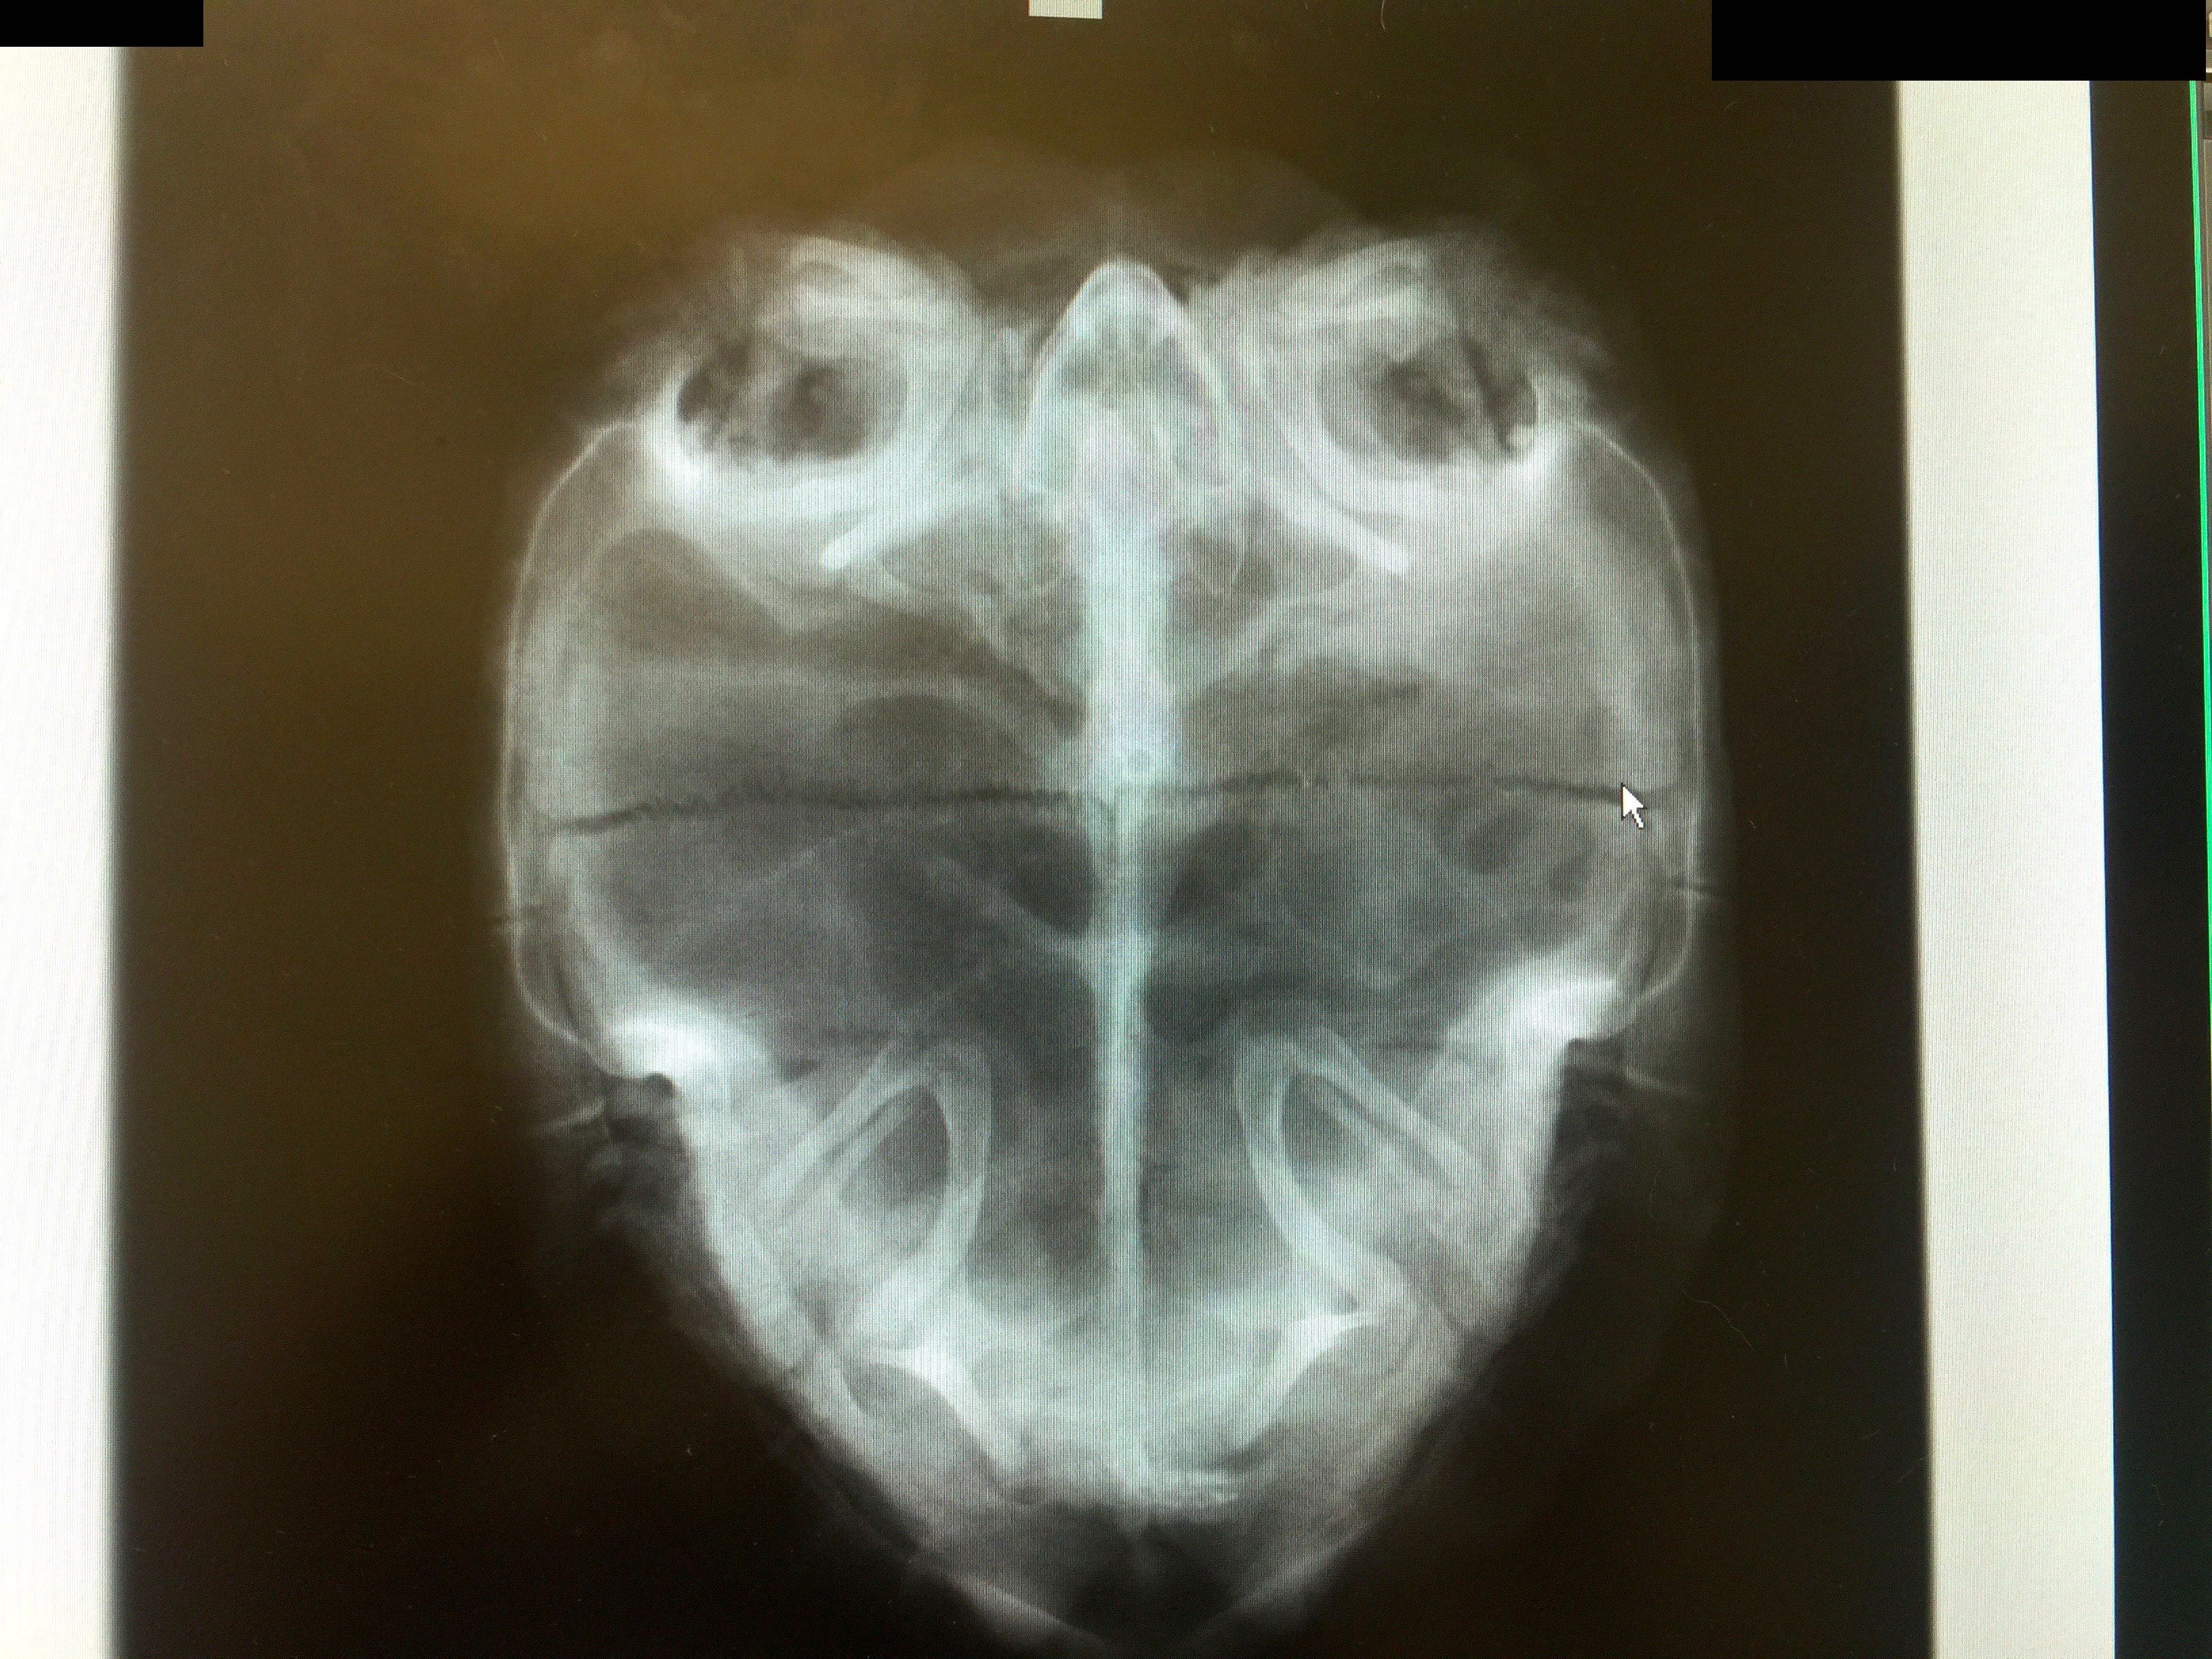

多くのトゲヤマガメを長期飼育されている亀友さんにアドバイスを頂き、まずは原因を絞るべくレントゲンを撮ることにしました。

撮影の結果

やはり、ストレスによる拒食症状となっているのでしょうか。